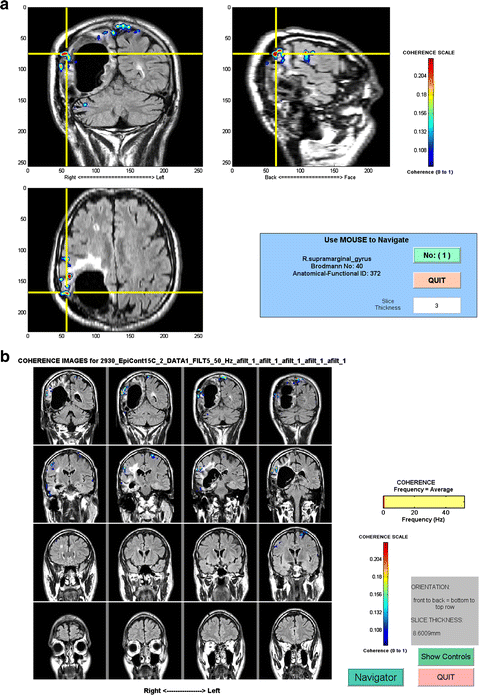

In the past 10 years, developments in the computational analysis of the source localization for MEG have advanced the ability for connectivity to be imaged directly into the specific regions of the brain (called Source space; Fig. 2). This source space method provides better anatomical localization as well as the ability to perform group analysis, as the data can now be averaged across a standardized space. The high temporal resolution of MEG allows for investigations of function and effective connectivity with millisecond precision. It is possible now to study the mechanisms by which information is exchanged across brain regions, including oscillatory and synchronized neuronal activity. There have only been a handful of coherence studies performed in the past 10 years using different inverse methods (dipoles, minimum norm or beamformers) to perform source space coherence analysis across many different brain disorders. All of these diverse investigations show that coherence imaging in Source space provides a wealth of new information on the integrity and strength of the functional connectivity in a patient’s brain networks.

Fig. 2

An illustration of Source space coherence mapping. MEG- CSI analysis of the locations of coherent activity in the brain of a patient with epilepsy. Top 15 axial slices are the view of the entire brain. The 3 MRI slices below indicate the top coherent location of brain activity in the Right supra marginal gyrus